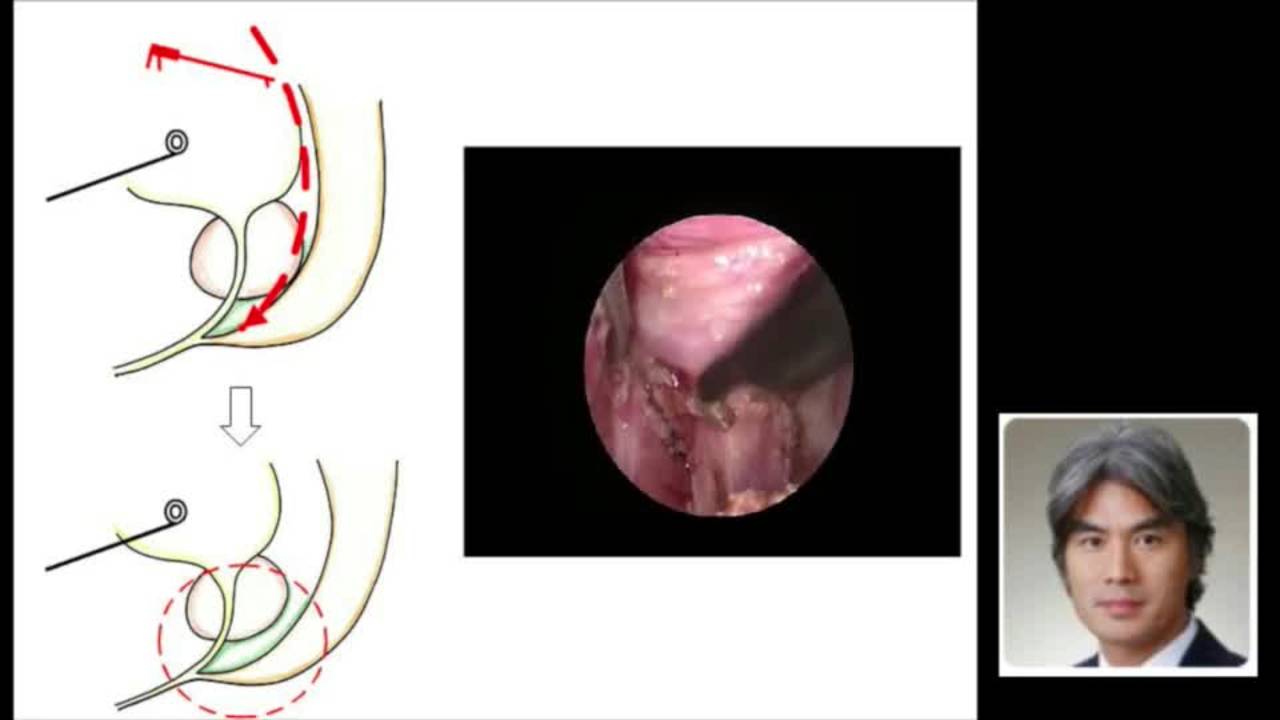

Technique: Laparoscopic-Assisted Pull-through for Imperforate Anus

Laparoscopic-Assisted Pull-through for high imperforate anus by Dr. Steven Rothenberg.